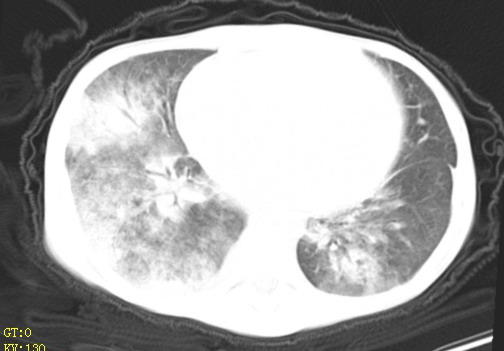

女,12岁,气促、咳嗽2天,3个月前查胸片示:两肺感染,急诊入院查ct,血常规等未检查。

左肺上叶改变考虑继发性肺结核,余双肺重症肺炎不排除h1n1。双侧胸腔少量积液。

1)考虑两肺感染性病变;建议抗炎治疗后复查。2)双侧少量胸腔积液。

双肺中下野不规则片絮状阴影,中外带明显,双侧胸腔少量积液,心影增大,心腔密度减低,隆突下及左侧气管旁见钙化淋巴结影,考虑双肺感染、心衰;建议结合临床除外h1n1并急性心衰,先心不能排除。

两肺多发片絮状模糊影,以下肺外带居多,内见支气管气像,纵膈窗未减影,两侧胸腔积液,心影增大,结合心超,支持重症肺炎,非常时期,甲型h1n1流感不排除。